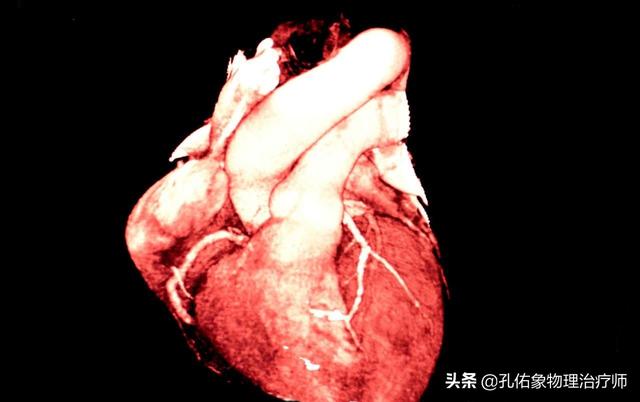

冠動脈性心疾患とは、冠動脈の動脈硬化が原因で起こる心臓病で、冠動脈の狭窄や閉塞により虚血、低酸素、心筋細胞の壊死が起こる。冠動脈疾患の診断には、臨床症状、臨床検査、心電図、冠動脈CT、冠動脈造影などの総合的な判断が必要である。

冠状動脈性心臓病は最も一般的な慢性疾患の一つであり、冠状動脈性心臓病は私たちの住民の主な死因の一つであり、冠状動脈性心臓病の重要性はこのように明らかである!冠状動脈性心臓病は非常に多く、現在わが国には1100万人の冠状動脈性心臓病患者がおり、冠状動脈性心臓病と診断された後、私たちは定期的に病院に行って検査を受けなければならないが、冠状動脈造影検査は一般的な検査方法である。この疑問について一緒に考えてみましょう。